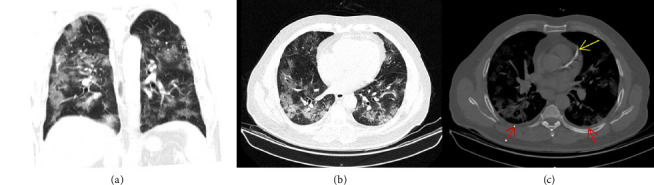

COVID-19 is associated with a hypercoagulable state, often managed with anticoagulation therapy to prevent thrombotic events. However, anticoagulation can lead to rare but serious bleeding complications. We present the case of a 62-year-old male with severe COVID-19 admitted to the intensive care unit (ICU) with shortness of breath, cough, and oxygen desaturation. Also, he had diabetes, undergoing treatment with Neutral Protamine Hagedorn (NPH) insulin, and ischemic heart disease. On the eighth day of his admission, he developed a spontaneous sublingual hematoma while on unfractionated heparin therapy. The patient was managed conservatively with blood pressure control, cold compresses, adjustment of anticoagulation and close monitoring with laboratory anticoagulation tests, and careful observation. Despite the hematoma's initial enlargement, he exhibited no respiratory distress, and the hematoma gradually resolved without surgical intervention. This case highlights the need for vigilant monitoring, careful management of anticoagulation, and a multidisciplinary approach in balancing the benefits and risks of anticoagulation in COVID-19 patients.

Abstract Image